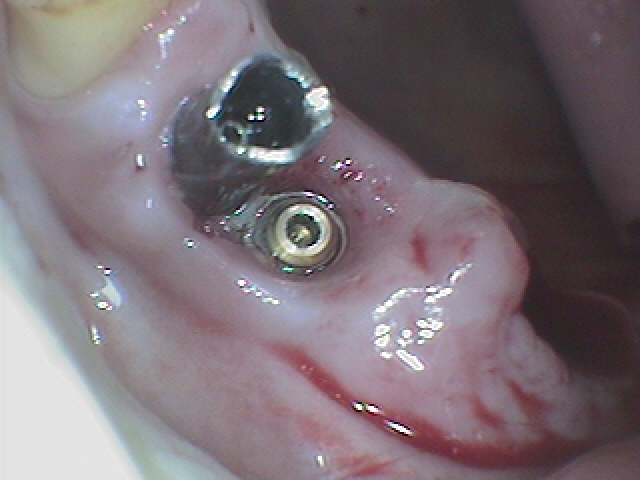

すぐに上部は取れました

アバットメントを外してみます

何のインプラントかもわからないものは触りにくいです

これが上部のクラウンになります